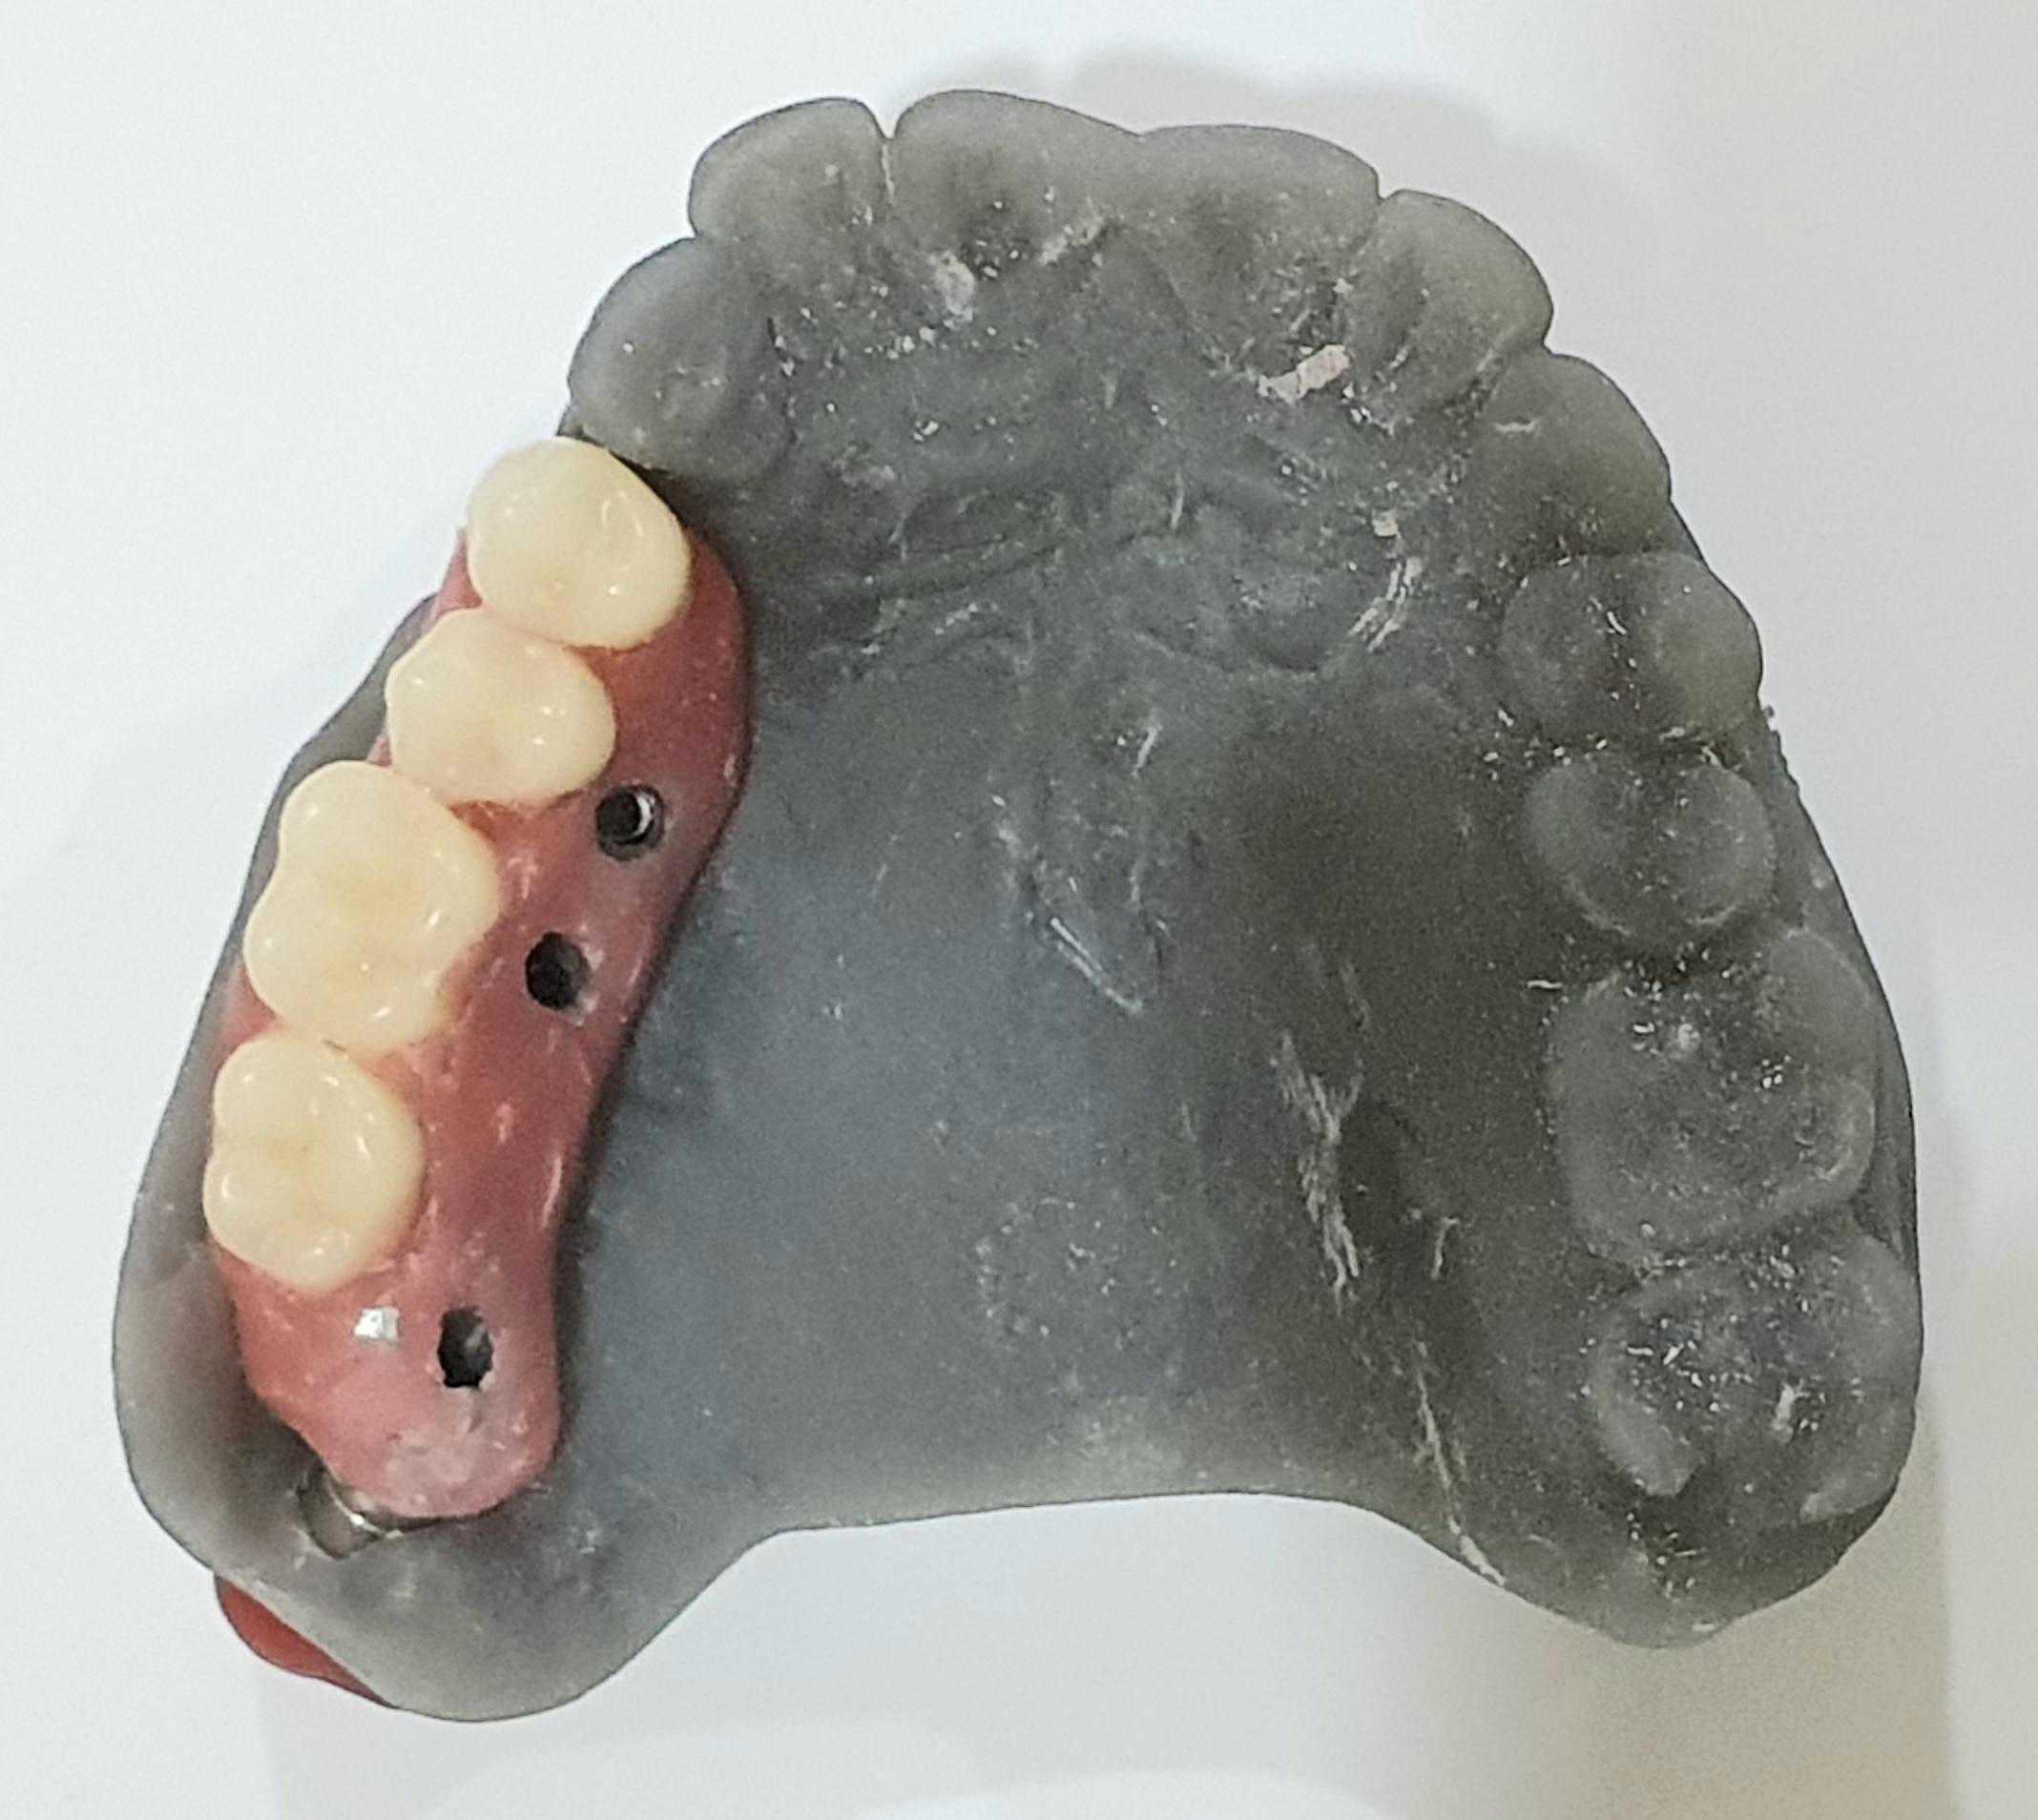

https://demo.discussdentistry.com/forums/topic/post-mucormycosis-avascular-necrosis-of-maxilla-rehabilitation-with-zygomatic/#post-24499 <![CDATA[Post Mucormycosis Avascular necrosis of maxilla, rehabilitation with Zygomatic]]> https://demo.discussdentistry.com/forums/topic/post-mucormycosis-avascular-necrosis-of-maxilla-rehabilitation-with-zygomatic/#post-24499 Thu, 25 Aug 2022 12:14:40 +0000 Sankalp Mittal

• 20210604_101325 (2)20210604_101317 (2)20210604_103315 (2)20210604_102857 (2)20210604_104202 (2)20210604_104853 (2)20210824_105656 (2)20210824_112353 (2)20210824_114957 (2)20210824_131302 (2)20210826_100648 (2)20210826_100749 (2)20210826_100919 (2)20210914_183943 (2)20211001_17535220211012_18543620211012_192043 (2)20211012_185627 (2)20211012_195430 (3)20211027_193725 (2)20211027_200729 (2)20211027_200919